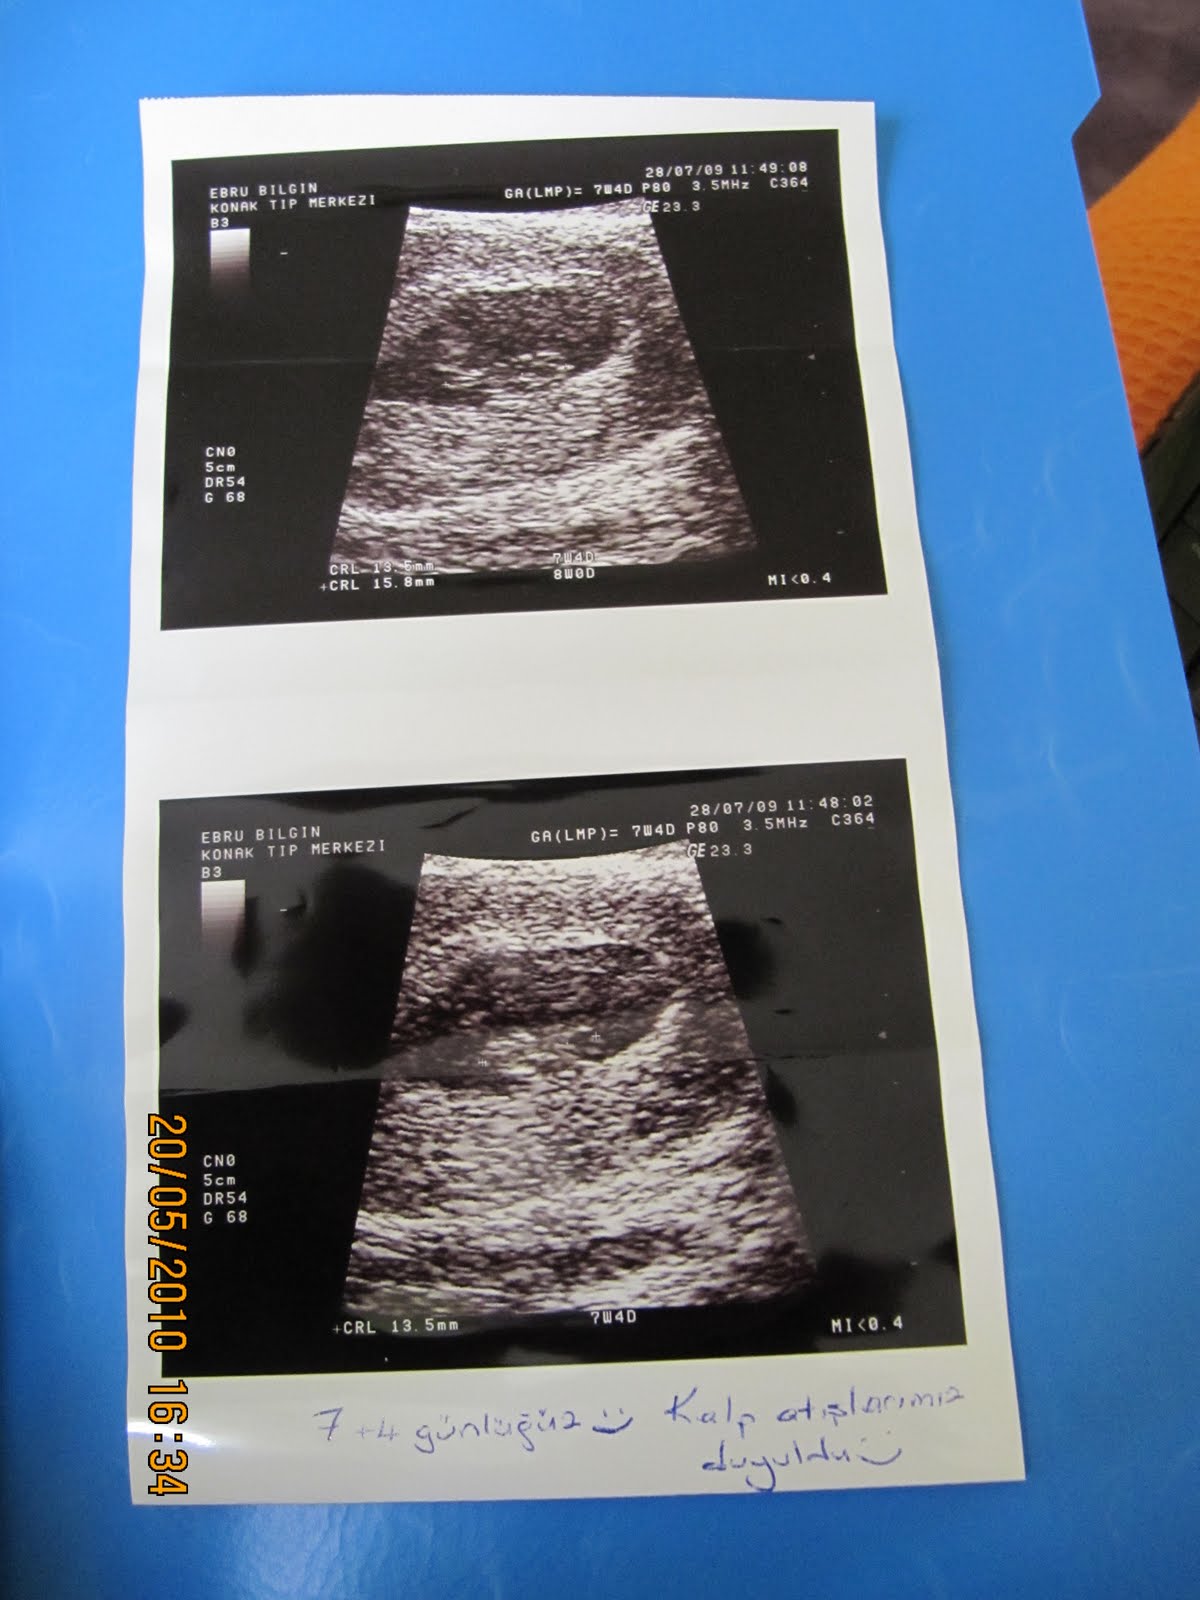

Bir hafta sonra yeniden gittim kese büyümüştü bebek gözükmüyordu boş gebelik olabilir dedi. Doktor hemen kürtaj ol dedi ama ben kabul etmedim. Haftalık hamileyim ama benim hamileliliğim normalden daha sıkıntılı ve ağrılı geçiyor iğnelerle duruyorum kalp atışı normal ama ben iyi değilim çok. Gebeliğin ilerlediği haftalarda kalp atışı duyulmamaya devam ederse bebeğin anne karnında öldüğü düşünülür. Bebeğin alınmayıp o şekilde anne rahminde bırakılması. Ben 8 haftalık hamileyim.az önce bebeğimin kalp atışlarını dinlemek için doktora gittim.

8 Haftalık Gebelik Bebeğin Kalp Atışı, Boyu, Kesesi

7 Haftalık Bebeğin Kalp Atışı Kaç Olmalı? Normal Değer

Aras Bilgin 39 haftalık muhteşem serüvenim))